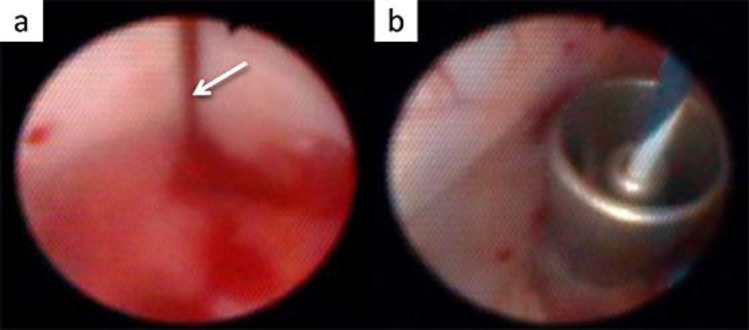

A 33-year-old male with an ileal conduit was referred to our department for the treatment of left renal calculi. After inserting a ureteral access sheath, a ureteroscopy-assisted retrograde nephrostomy was made. Percutaneous nephrolithotomy was successfully achieved using this nephrostomy.